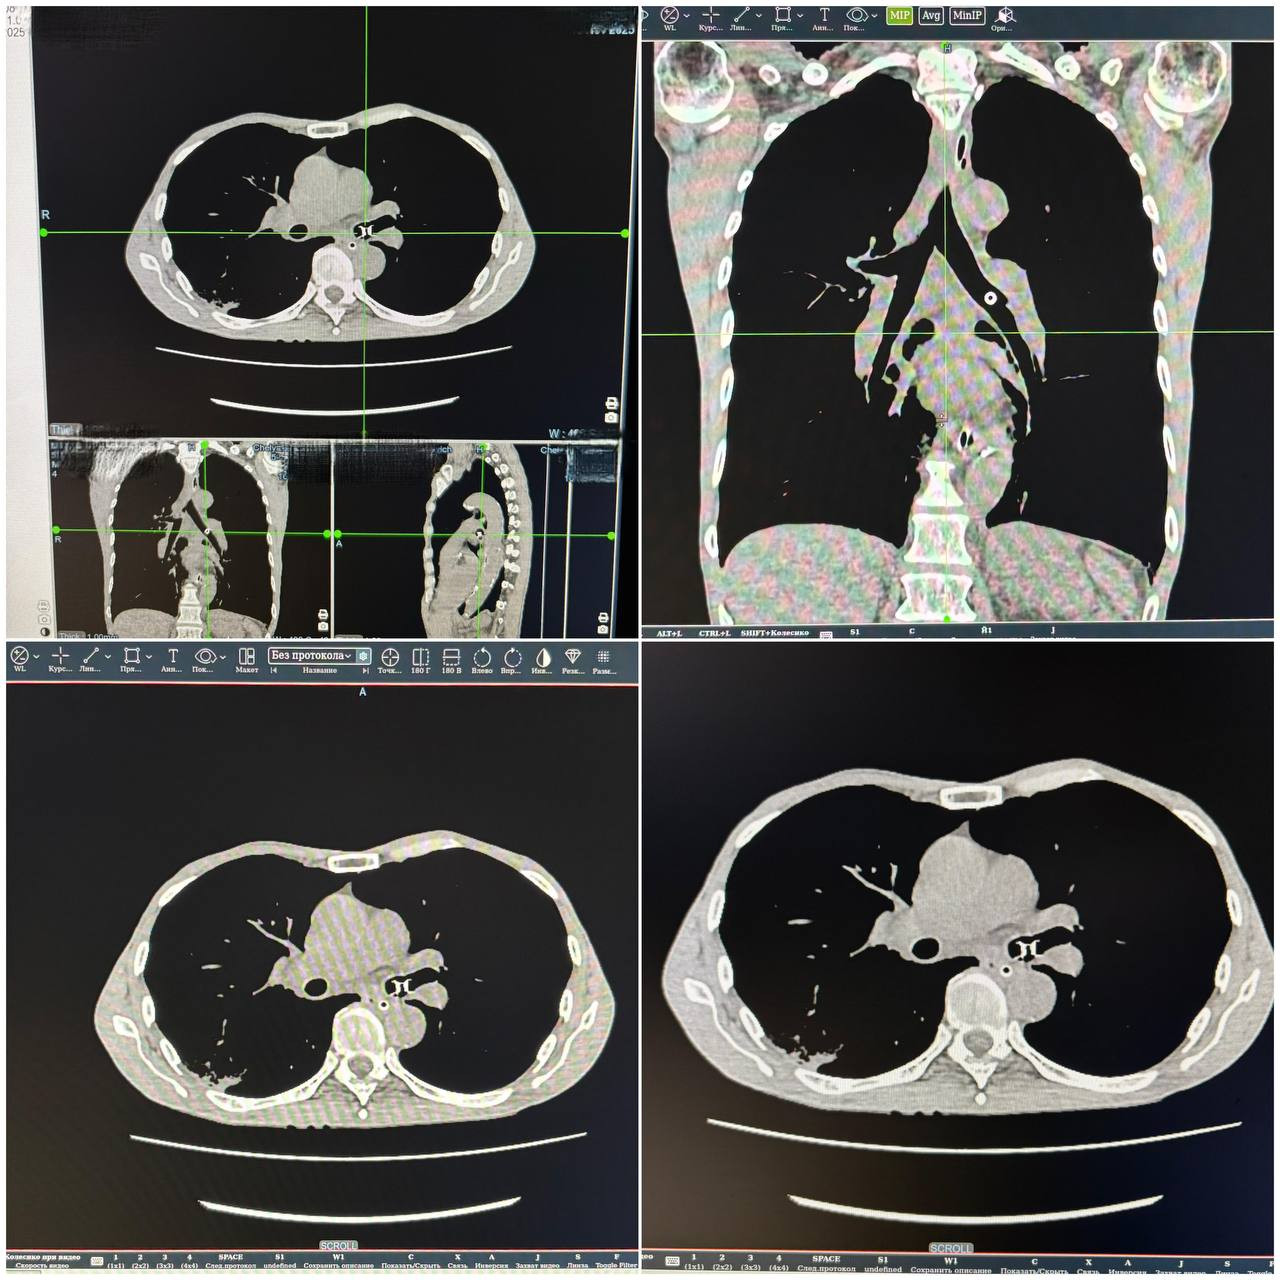

Мужчина поступил в реанимацию городской больницы Челябинска с жалобами на одышку и удушье.

Мультиспиральная компьютерная томография показала наличие инородного тела в левом бронхе. Выяснилось, что в лёгкие «провалился» голосовой протез, который пациенту установили ранее после операции на трахее. В течение получаса посторонний предмет удалось извлечь.

«Левое лёгкое у него было полностью перекрыто, дышал правым лёгким. Попадание инородных тел в нижние отделы дыхательных путей – очень опасное состояние. Извлечь такие «подарки» бывает непросто. Нам повезло, что предмет застрял в левом главном бронхе, там, где широко и удобная форма для захвата», – комментирует Юлия Клепинина, врач-эндоскопист.